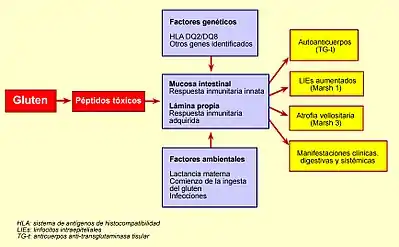

La enfermedad aparece en individuos genéticamente predispuestos. Su base hereditaria más conocida se relaciona con el sistema de antígenos leucocitarios de histocompatibilidad (HLA) de clase II y sus marcadores más habituales son el HLA-DQ2, que es el principal, apareciendo en el 85-95 % de los casos, y el HLA-DQ8 en una menor proporción (5-10 % de los casos), muy lejana del anterior.[27]

Aparte del gluten, entre los factores ambientales que pueden desempeñar un cierto papel en el desencadenamiento y/o aparición de la enfermedad celíaca, se encuentran la lactancia materna, que en general retrasa (aunque no previene) la aparición de la enfermedad, la edad de introducción de los alimentos con gluten en la dieta del bebé, ciertas infecciones intestinales o los viajes a países tropicales o subdesarrollados, así como algunas intervenciones quirúrgicas abdominales en el adulto.[19][27]

La celiaquia se desencadena en personas genéticamente predispuestas como consecuencia de la interacción entre el gluten y otros factores ambientales exógenos, y la respuesta inmunitaria. Se induce por la ingesta de gluten, a través de una fracción denominada gliadina.[27]

La gliadina es la fracción soluble en alcohol del gluten. Es una proteína rica en residuos de glutamina y prolina, y contiene la mayor parte de los productos tóxicos. Las moléculas de gliadina no digeridas, tales como la fracción alfa (que contiene 33 aminoácidos), son resistentes a la degradación por las secreciones gástrica, intestinal y pancreática. La existencia de un aumento de la permeabilidad en la barrera epitelial del intestino delgado debido al aumento de la señalización por parte de la zonulina (independientemente de la predisposición genética, es decir, tanto en celíacos como en no celíacos la gliadina aumenta la síntesis intestinal de zonulina ) permite que estos péptidos la atraviesen y reaccionen con las células presentes en la submucosa o lámina propia, lo cual desencadena una respuesta inflamatoria mediada por linfocitos T colaboradores tipo 1. Esta respuesta se caracteriza por la producción de un proceso inflamatorio, desencadenado por linfocitos CD4+ a nivel de la lámina propia o submucosa, que reconocen a los péptidos de la gliadina que son presentados por las células dendríticas ayudadas por moléculas HLA de clase II, del tipo DQ2 y DQ8. A continuación, se libera una serie de citoquinas pro-inflamatorias tales como el interferón gamma (IFN-γ) y el factor de necrosis tumoral alfa (TNF-α), entre otras, que favorecen la producción de la hiperplasia de criptas y la aparición de la lesión epitelial.[27]

Los péptidos de gliadina también tienen la capacidad de activar la respuesta inmunitaria innata, caracterizada por una expresión aumentada de interleuquina 15 por parte de los enterocitos, lo que provoca la llegada y estimulación de los linfocitos intraepiteliales que expresan el receptor NK-G2D, un marcador natural de las células citolíticas (natural killer [NK]), las cuales son citotóxicas y destruyen las células del epitelio intestinal. El mecanismo de interacción entre los procesos que se producen en la submucosa y en el epitelio todavía no está del todo aclarado.[27]

Las lesiones que la celiaquía provoca en el intestino delgado de un celíaco no se limitan a la presencia de atrofia de las vellosidades intestinales, sino que con frecuencia consisten en cambios mínimos, con inflamación leve o moderada, especialmente en los niños mayores de dos años y los adultos.[19][50][51][52] [40]

Cursa frecuentemente con serología negativa (ausencia de anticuerpos específicos en sangre), especialmente la anti-transglutaminasa,[19][50][40] ya que está elevada en relación con la presencia de atrofia de vellosidades, que no se encuentra en jóvenes ni en adultos por lo general.[40][53][54][55][56][57]